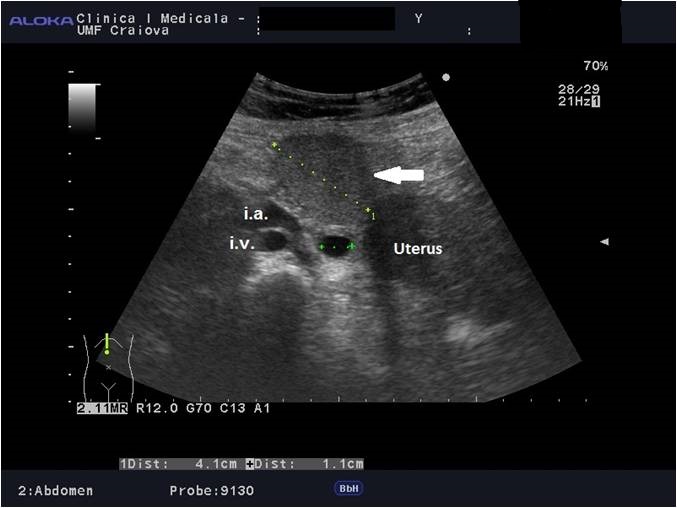

Unexpected finding of large, multifocal focal fatty infiltration of the liver in a patient with hypothyroidism and coeliac disease [Jun 2019]

Case courtesy of Larisa Săndulescu MD